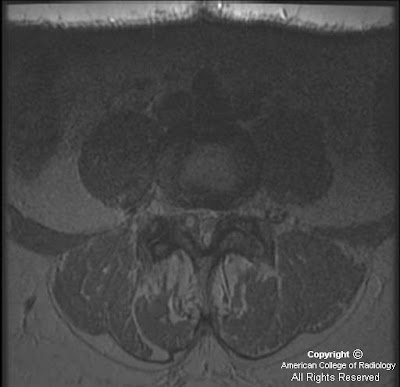

Facet Synovial Cyst